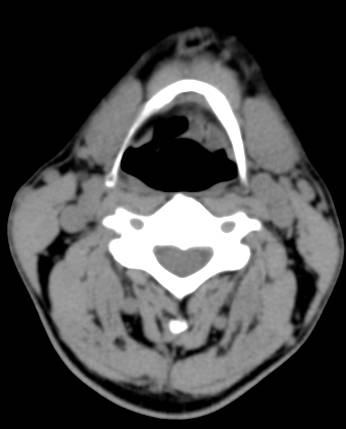

左侧会厌间隙见少许软组织密度影,增强可见环形强化,壁薄。双侧颈部未见明显肿大淋巴结。

(1)弥漫型,喉粘膜弥漫性、不对称肿胀增厚,以会杓皱襞、会厌、杓状区常见,喉结核关于喉旁间隙或会厌前间隙是否侵润,文献中有不同意见。(2)局灶性(肿块型),可见软组织肿块,密度欠均匀,增强可见环形强化。